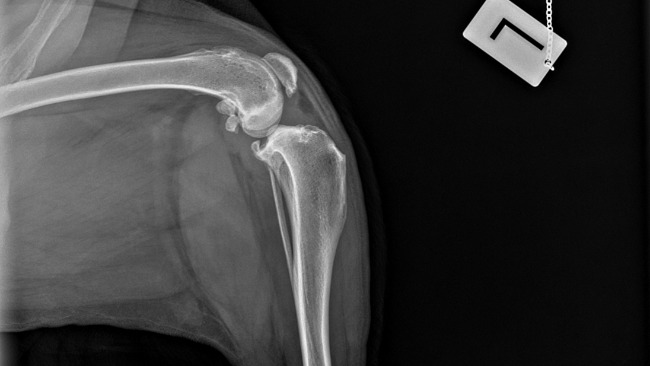

To tak dzielny, wspaniały, kochany zwierzak, że ciężko uwierzyć, że kilka dni temu przeszedł taką ciężką operację.

Nóżka Kokoszka, choć nadal obrzęknięta, dobrze się goi i nasz dzielny psiak stawia na niej swoje wielkie łapeczki.

Sam Kokosz jest teraz taki uśmiechnięty i pogodny, że wiemy, że decyzja o wykonaniu u niego pierwszej z trzech operacji łapek była słuszna i najlepsza.

Fot. Droga chłopaków do równowagi psychicznej. Wizyty w gabinecie lek.wet.